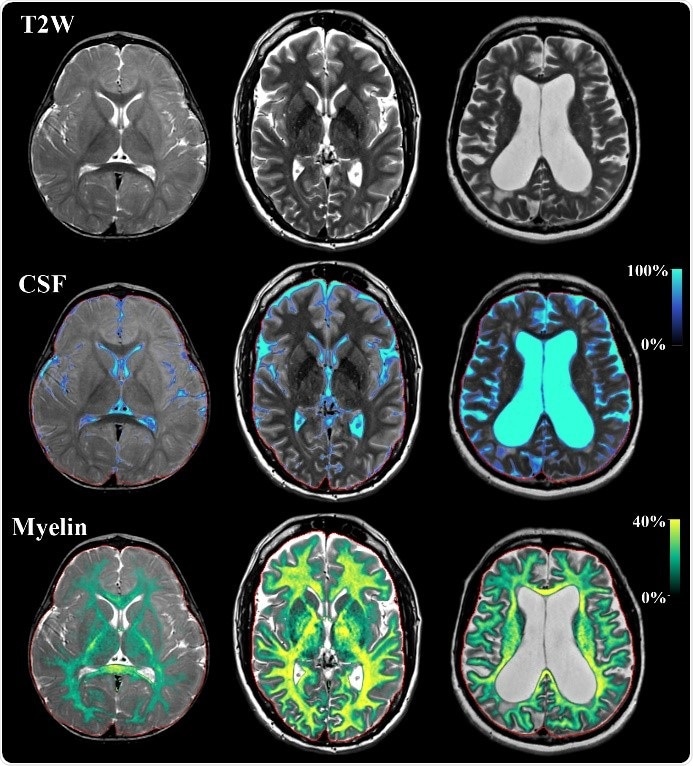

Example of SyMRI imaging on three subjects with the age of 1 year, 43 years and 73 years old. Displayed are synthetic T2-weighted images of an axial slice of the brain. On the same slice a tissue segmentation is performed of cerebrospinal fluid (CSF) and of myelin. Using this map, radiologists can follow signal changes, brain volume and the state of myelination. The acquisition takes 5 minutes for full coverage of the brain.